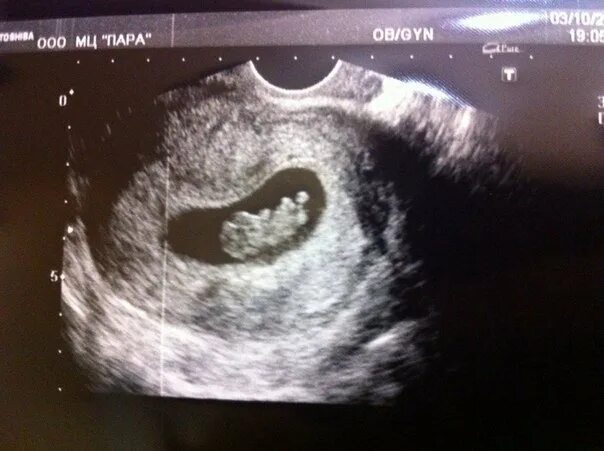

Узи 6 месяцев